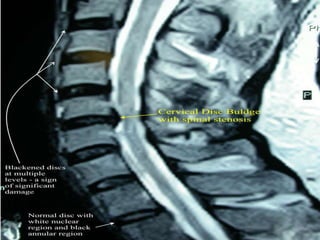

X-Ray : lumbo-sacral spine;

 Narrowed disc spaces.

 Loss of lumber lordosis.

 Compensatory scoliosis.

CT scan lumber spine;

 It can show the shape and size of the spinal canal, its contents, and the

structures around it, including soft tissues.

 Bulging out disc.

MRI lumber spine;

 Intervertebral disc protrusion.

 Compression of nerve root.

Myelogram;

 pressure on the spinal cord or nerves, such as herniated discs, tumors,

or bone spurs.